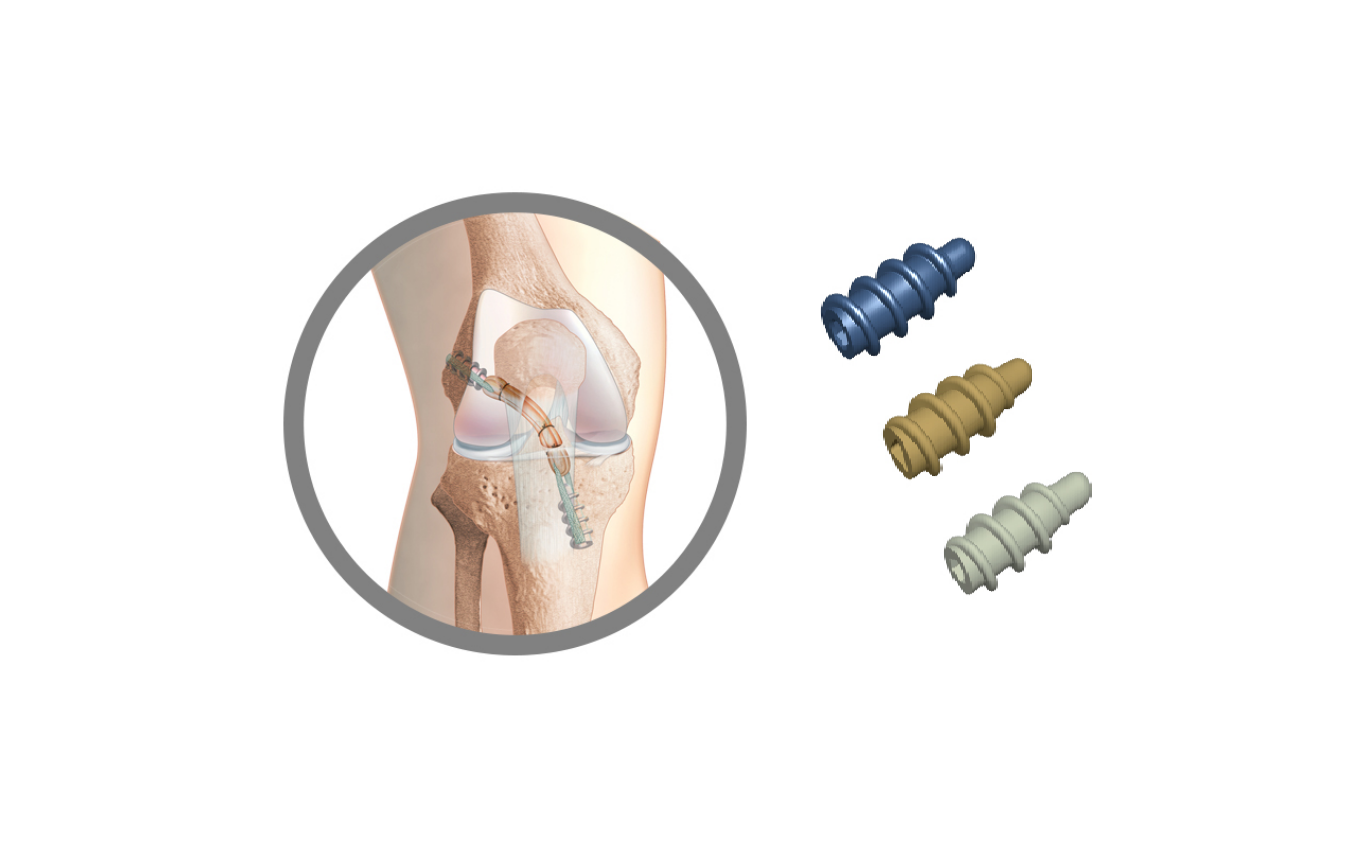

TLS é um sistema de reconstrução dos ligamentos cruzados do joelho por enxerto curto.

Sistema TLS (Tape Locking Screw)

Os princípios fundamentais do conceito de TLS são:

Transplante :

– um tendão feita,

– preparação circuito curto fechado (4 cordões tendinosos, DT4),

– pré-esforço,

– introdução através primeiro artroscópica (tudo dentro),

– em encaixe por pressão nos compartimentos,

– contactar 100% osso.

Os túneis ósseos:

– eixos de túneis independentes, obtidos por apontando para dentro (para-in),

– de baixo calibre (4.5 mm)

– retrógrado escavação manual de baias osso receptor do enxerto,

– bancas adaptado para diâmetros do enxerto.

Fixação:

– Suspensão da alça do ligamento pelos relés têxteis,

– Parafusos TLS para bloqueio das tiras, colocados de fora para dentro.

O sistema de fixação TLS inclui:

– um parafuso TLS (ø 10 mm, lg 20 ou 25 mm) disponível em titânio, espiada ou biocomposto.